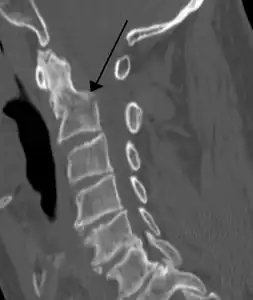

On CT scan or X-ray, a cervical fracture may be directly visualized. In addition, indirect signs of injury by the vertebral column are incongruities of the vertebral lines,[7] and/or increased thickness of the prevertebral space:[8]

X-ray of normal congruous vertebral lines